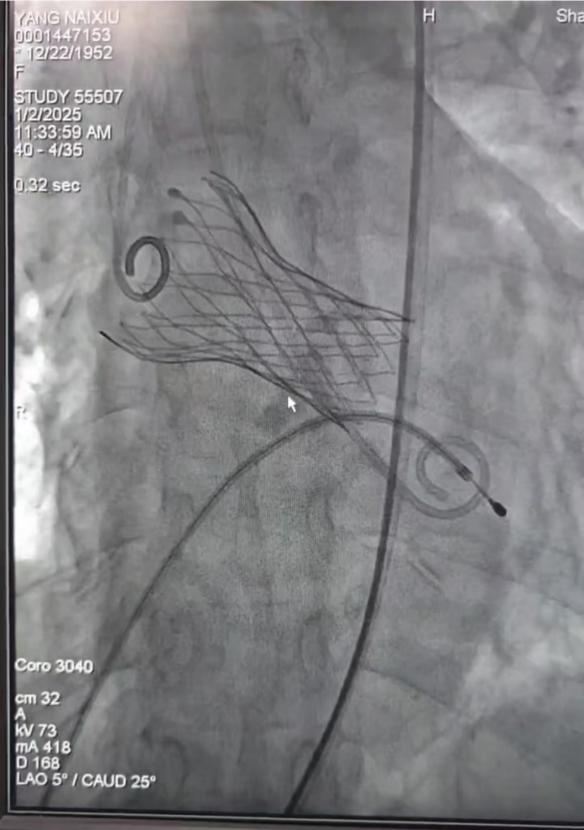

1月2日,新年的第一个工作日,在科室精心准备及心内一科王军奎主任团队的支持下,经导管主动脉瓣置换术(TAVR)手术顺利开台。接受手术的是一位来自宝鸡市岐山县的72岁老年女性患者,患者近2年来反复胸闷气短,备受疾病困扰,心脏彩色多普勒超声提示主动脉瓣重度狭窄,最大跨瓣压差达137mmHg,瓣上最大血流速度585cm/s。姜馨主任主持多学科讨论,审慎评估病情,确定为患者行TAVR手术的治疗方案。经积极准备,张炜副主任医师带领心内三科TAVR团队与心内一科潘硕博士团队密切合作,顺利完成手术。患者术后胸闷气短症状明显好转,复查心脏超声显示主动脉瓣人工瓣膜固定良好,最大跨瓣压差17mmHg,瓣上血流速度基本正常。患者术后恢复良好,已顺利出院。

图1 TAVR手术